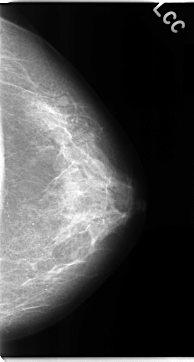

C_0068_1.LEFT_CC

LEFT_CC LINES 4696 PIXELS_PER_LINE 2512 BITS_PER_PIXEL 12 RESOLUTION 50 NON_OVERLAY